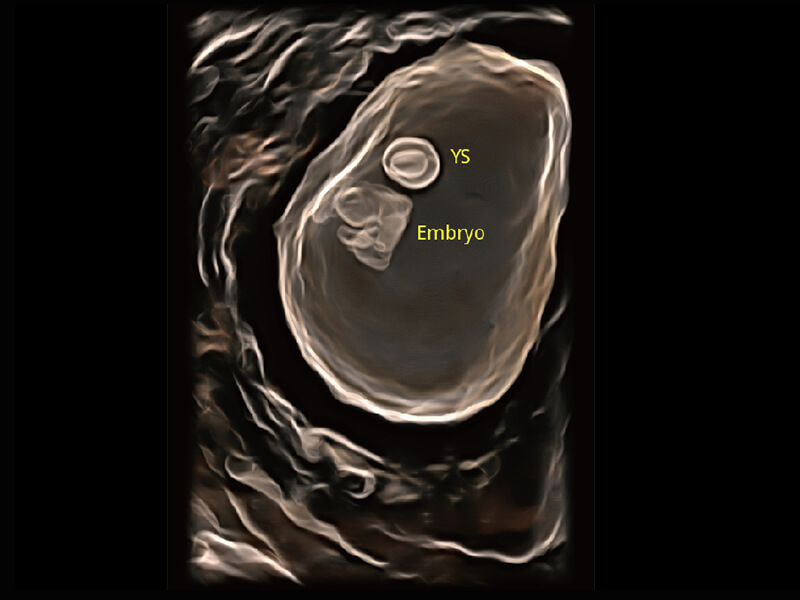

高分辨率容积成像 栩栩如生

超宽频带技术,为容积成像带来优质的二维图像基础,为您呈现丰富的结构细节,栩栩如生地展示宝宝的宫内形态以及各种组织的立体结构。